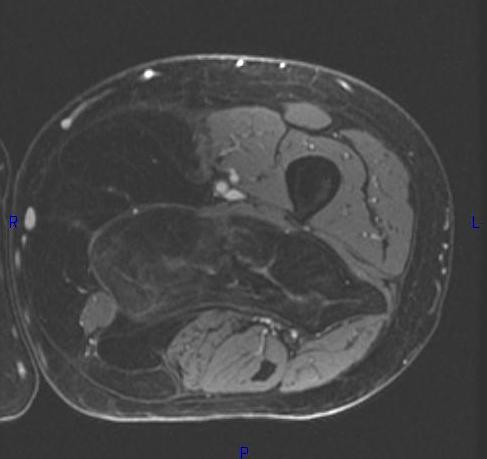

MRI (Fig. 1, 2, 3 and 4)

• Large encapsulated lipomatous mass. (Fig. 1, 2, 3 and 4)

• MRI does not appear homogeneous. (Fig. 4)

Fig. 2-4 MRI: Coronal T2-weighted fat suppressed (Fig. 2) and Axial T2-weighted FS (Fig. 3) shows low intensity signal isointense with fat. Adypocitic lesion with fatty signal is located in the posterior and medial compartment of the thigh. Thickened septa and nodularity enhances on post contrast images. (Fig. 4)